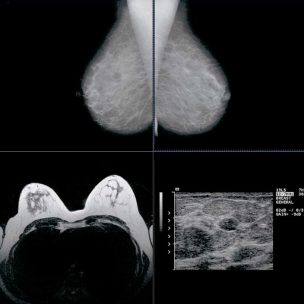

- ALIA Health, spin-off de TecSalud, y ÜMA Tech IA, Partner de Servicios de Google Cloud para el sector salud en Latinoamérica, desarrollan ALIA Health Risk Platform, una plataforma basada en inteligencia artificial que permite anticipar el riesgo de cáncer de mama a partir de mamografías.

En un contexto donde la mortalidad por cáncer de mama en México ha alcanzado uno de sus niveles más altos en décadas —con una tasa de 19.8 defunciones por cada 100 mil mujeres—, ALIA Health y ÜMA Tech IA anunciaron el desarrollo conjunto de ALIA Health Risk Platform, una plataforma basada en inteligencia artificial orientada a la predicción y estratificación del riesgo de cáncer de mama a cinco años, a partir de mamografías de la práctica clínica habitual.

Mammorisk+ es un modelo predictivo, entrenado con datos reales de práctica clínica y diseñado para estimar la probabilidad futura de desarrollar cáncer de mama en un horizonte de cinco años, exclusivamente en mujeres con mamografías sin hallazgos sospechosos. Su objetivo es actuar antes del diagnóstico, en la etapa donde se definen estrategias de prevención, seguimiento y personalización del tamizaje.